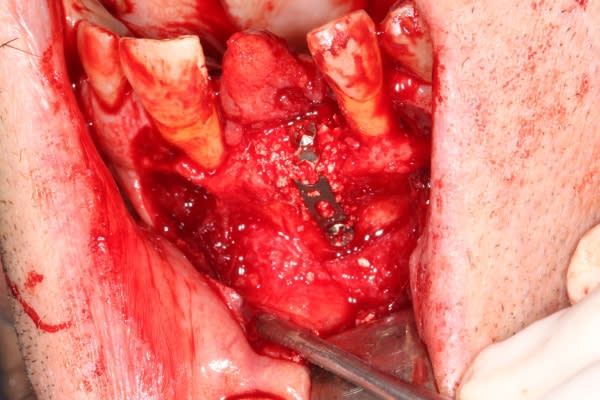

Extraction implantation immédiate mais il y a au moins 7 spires à nue... (photo 1, 2)

dans cette technique un pilier de 2mm de haut est vissé sur l'implant, ce pilier contient un orifice qui permet de transfixer la barre (photo 3,4)

l'espace créé est rempli avec un biomat et le tout est recouvert d'une membrane